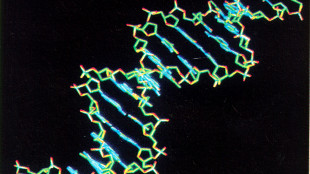

L'invecchiamento del Dna alla base dell'Alzheimer, lo studio italiano

Centrale il danneggiamento dei telomeri, si aprono nuove prospettive terapeutiche